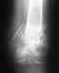

Месяц назад сломал вроде как медиальный надмыщелок,отходил в гипсе 1 месяц и неделю.

По итогу один врач говорит,что кость не срастается,но снял гипс.При всем при этом сказал,чтобы я разрабатывал руку и если за 2 месяца она не срастётся,то придётся убирать обломок.Другой же врач говорит,что туда не надо лезть,все должно зажить и также посоветовал разрабатывать.Кому верить и что делать?